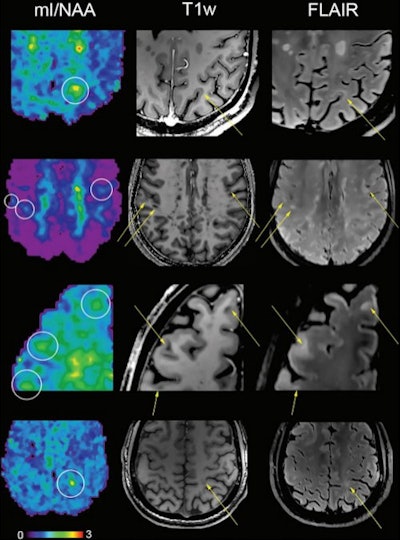

In the current study, proton MR spectroscopy was performed on a 7-tesla scanner using a technique called free-induction decay MR spectroscopic imaging, with 2 x 2-mm in-plane spatial resolution. For the study, the investigators used the technique to compare differences in normal-appearing white matter and cortical gray matter in the brains of 65 MS patients and 20 healthy controls.

The group found the following brain differences in patients with MS:

- Lower levels of an amino acid derivative called N-acetylaspartate, which is associated with compromised integrity of neurons

- Higher levels of myo-inositol, which is involved in cell signaling; increased levels indicate significant inflammatory disease activity

- Metabolic changes in normal-appearing white matter and cortical gray matter